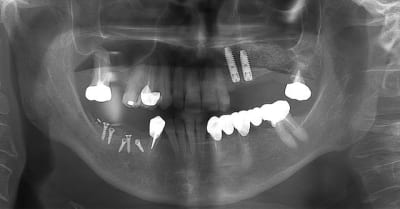

13/12/2011 à 05h00

oups ! j'avais oublié les opt

merci à ceux qui ont déja pratiqué cette technique de me dire quel est leur mode opératoire. les résultats, les p'tits trucs pour faire avancer la science quoi ...

13/12/2011 à 07h40

je trouve ça très intéressant, attendons la suite.

13/12/2011 à 11h51

joli!

As-tu fait de l'ostéotension ou similaire pour augmenter l'apport sanguin ?

As-tu utiliser du PRF pour améliorer ostéoconduction?

comment as-tu obtenu la laxité gingivale pour fermer sans tension?

n'as-tu pas peur que malgré tout ça bouge avec la mastication?

Combien de temps laisses-tu cicatriser avant de réintervenir?